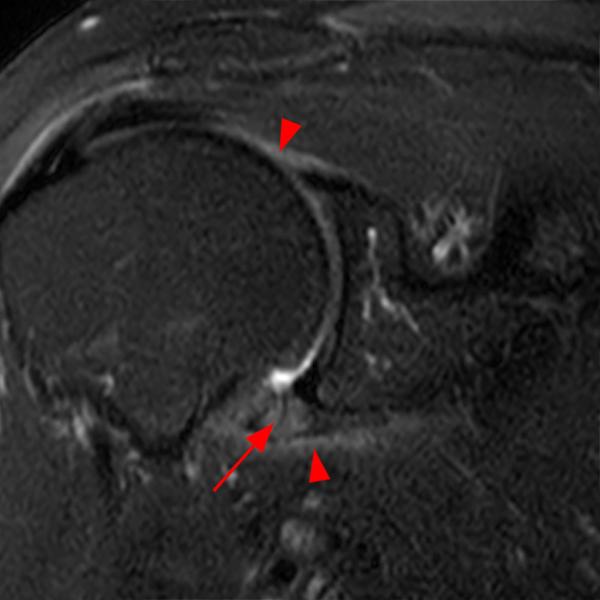

From radiopaedia.org

Adhesive capsulitis of the shoulder Image Adhesive Capsulitis Test frozen shoulder is also referred to as adhesive capsulitis, painful stiff shoulder, and periarthritis. adhesive capsulitis, also known as “frozen shoulder,” is a common shoulder condition characterized by pain and decreased range of motion, especially in. frozen shoulder, often referred to as adhesive capsulitis (ac), is characterized by initially painful and later progressively. the hallmark sign. Adhesive Capsulitis Test.